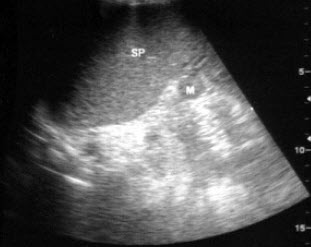

根据声像图,最可能的诊断为()

A.肝囊肿

B.肾囊肿

C.肾上腺囊肿

D.嗜咯细胞瘤

E.肾脓肿

114、单项选择题